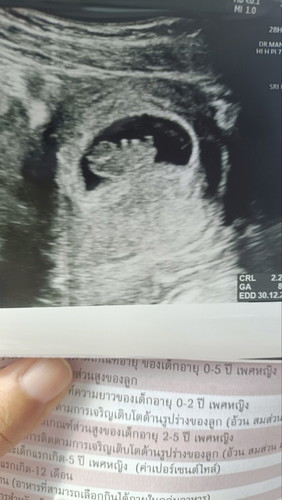

วันนี้ไปอัลตร้าซาวด์ ครั้งแรก อายุครรภ์ 9w5วัน

ตอนแรกคิดว่าท้องลมรึป่าว ไม่ค่อยแพ้เท่าไหร่ !! แอบกังวล แต่พอซาวด์ดู เรารู้สึกเห็นชัดมาก ไม่รู้คนอื่นเห็นชัดแบบนี้มั้ย ดีใจจังค่ะ มีอะไรอยู่ในท้องด้วย 🥰🥰🥰

ซาวนด์เจอครั้งแรกตอน 5W3D ภาพล่าสุดก็ 9W4D น้องขยับตัวโชว์คุณหมอแล้วด้วย แต่คุณแม่ยังไม่รู้สึกเลย ตอนนี้ 10W6D แล้ว ไม่ค่อยแพ้เหมือนกัน แต่กลัวจะไปแพ้ตอนไตรมาสที่สอง #ทีมธันวาคม ขอให้คุณแม่และน้องแข็งแรงนะคะ